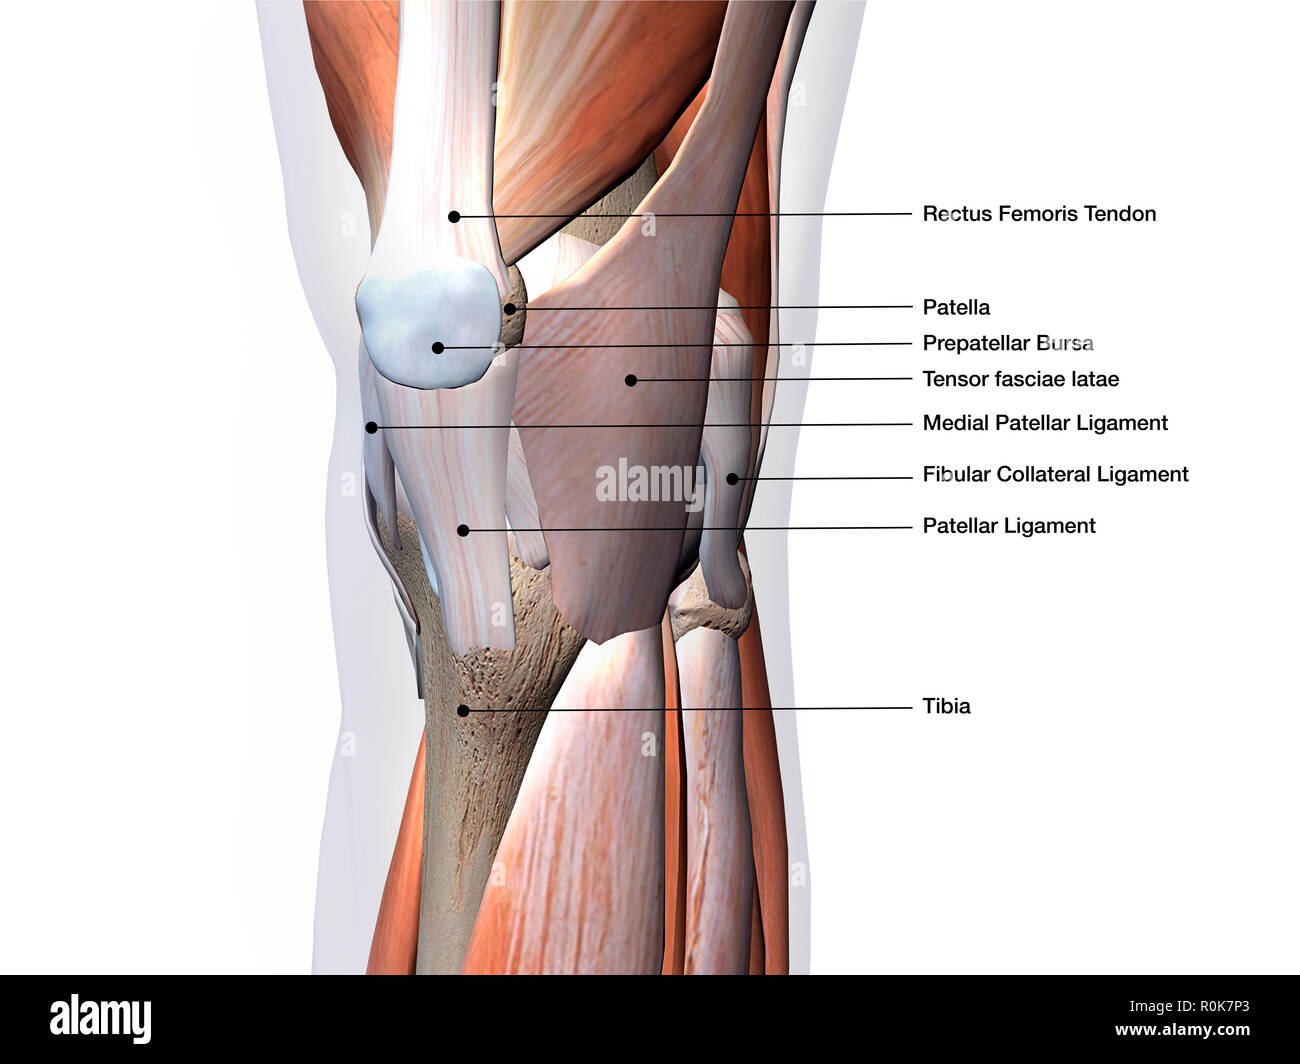

Knee joint showing muscles and ligaments with labels. Stock Photohttps://www.alamy.com/image-license-details/?v=1https://www.alamy.com/knee-joint-showing-muscles-and-ligaments-with-labels-image224157979.html

Knee joint showing muscles and ligaments with labels. Stock Photohttps://www.alamy.com/image-license-details/?v=1https://www.alamy.com/knee-joint-showing-muscles-and-ligaments-with-labels-image224157979.htmlRFR0K7P3–Knee joint showing muscles and ligaments with labels.